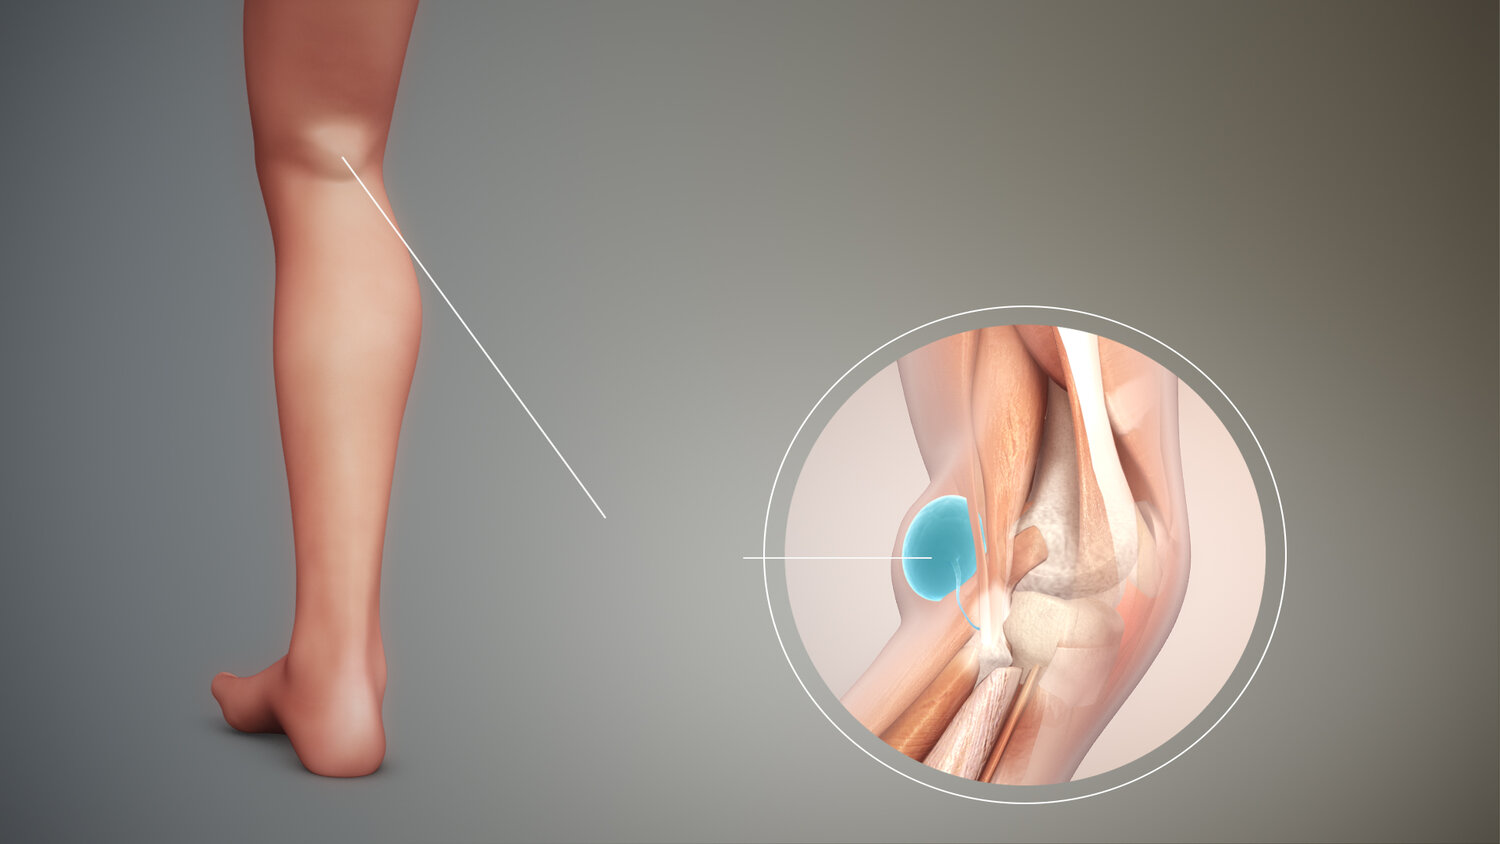

کیست بکر پشت زانو چیست؟ baker cyst

کیست بکر، که به آن کیست پوپلیتئال نیز گفته میشود، یک کیسه پر از مایع است که در پشت زانو ایجاد میشود. این کیست در اثر افزایش مایع مفصلی در زانو به وجود میآید و معمولاً در نتیجه مشکلات زمینهای مانند آرتروز، آسیبهای زانو یا التهابهای مفصلی رخ میدهد.

در بسیاری از موارد، کیست بکر کوچک بوده و ممکن است هیچ علامتی نداشته باشد، اما اگر بزرگ شود، میتواند علائم زیر را ایجاد کند:

تورم پشت زانو: ممکن است تودهای نرم یا سفت را در پشت زانو احساس کنید.